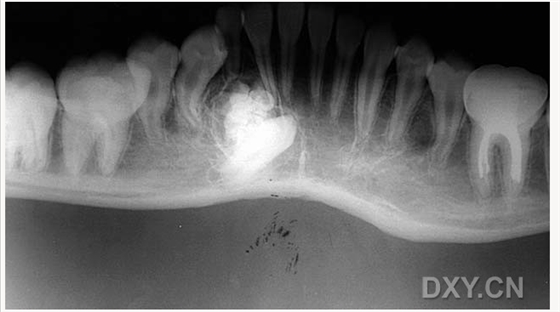

含牙囊腫

大理石骨?。ㄏ骂M骨有明顯的骨化影像,恒牙埋伏)

鼻竇炎(注意不要誤診呀)

良性成牙骨質(zhì)細(xì)胞瘤